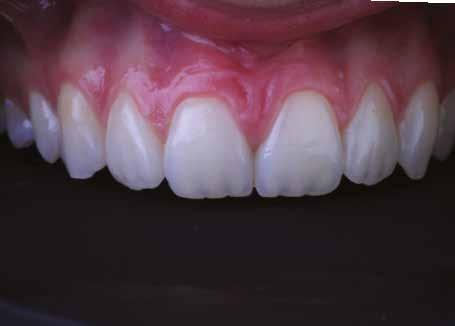

Egy 30 éves, negatív kórtörténettel rendelkező beteg azzal a kéréssel fordult hozzánk, hogy cseréljük ki az UR1 traumája után, 10 évvel korábban készült korábbi kompozit-helyreállítást.

A klinikai vizsgálat során az UR1 reagál a viabilitási tesztre, és az ugyanazon a napon készült röntgenfelvételen nem mutat periapikális elváltozásokat (1. ábra).

Az UR1 elszíneződött, és palatálisabb helyzetben van, mint az ellenoldali központi UL1 (2. ábra)

Az esztétikai elemzés a gingivális zenit aszimmetriáját mutatja az UR1 és az UL1 között. Parodontális szonda segítségével, plexusérzéstelenítés után, az IA

típusú funkcionális hám megváltozott passzív erupcióját igazoljuk Coslet és mtsai. osztályozása szerint (3. ábra)

A lehető legkonzervatívabb helyreállító kezelés elvégzése érdekében a páciensnél, figyelembe véve a megtartott fogelem korát és vitalitását, a tervezés és a diagnosztikai felviaszolás után a közvetlen kompozit-helyreállítás elvégzése mellett döntünk.

A kezelés napján, helyi plexusérzéstelenítést követően, az UR1-et kofferdámmal izoláljuk, kiterjesztve az izolációt az első premolárisokra (4. ábra)

Ezt követően eltávolítjuk a törött kompozt-helyreállítást, és az előkészített fogon rövid ferdére preparálást készítünk, majd az UR1 teljes felületén homokfúvást végzünk 27 μm-es alumínium-oxid porral (5. ábra)

A megváltozott passzív erupció korrigálása érdekében úgy döntöttünk, hogy a fog kiemelkedési profilját a vesztibuláris kidomborodás hangsúlyozásával és az ellenoldali elemmel való szimmetriára törekvéssel újra létrehozzuk. Erre a célra

egy előre megformázott fémmatricát használunk, amelyet két ékkel blokkolunk.

A matrica adaptálása után az adhéziós eljárásokat egy 3 lépéses etch&rinse rendszerrel végezzük. Minden egyes lépést 40 másodperces, UV-fénnyel történő polimerizálás követ (6. ábra)

A vesztibuláris kiemelkedési profilt zománcszínű kompozittal (a TOKUYAMA DENTAL ESTELITE ASTERIA WE termékével) állítjuk helyre (7. ábra).

A diagnosztikai felviaszolás szilikonindexének elkészítése után a palatinális falat zománcszínű kompozittal (a TOKUYAMA DENTAL ESTELITE ASTERIA WE termékével) helyreállítjuk (8. ábra)

Ezt követően helyreállítjuk a dentin anatómiáját a mamelonok reprodukálásával egy átlátszatlan dentinszínű kompozittal (a TOKUYAMA DENTAL ESTELITE SIGMA QUICK OA2 termékével); ez a szín alapvető fontosságú lesz a diszkromatikus elem színének korrigálásához is (9. ábra) Világoskék és fehér hatású árnyalatokat (a TOKUYAMA

DENTAL ESTELITE COLOR termékét) alkalmazunk az opá-

losság emulálásához az incizális területen (10. ábra)

A rétegezést egy zománcszín (a TOKUYAMA DENTAL ESTELITE ASTERIA WE terméke) használatával végezzük a vesztibulárisban, egyszeri hozzáadással. A vesztibuláris felületet háromdimenziós térfogatban modellezzük és vezéreljük annak érdekében, hogy a lehető legkevesebb végső kiigazítás legyen. Ezután 20 másodpercig polimerizáljuk, majd 40 másodpercig polimerizáljuk vesztibulárisan és palatinálisan, miután bevontuk őket gliceringéllel a kompozit hibrid rétegének elkerülése érdekében (11. ábra).

A finírozási és polírozási eljárásokat úgy végezzük, hogy megpróbáljuk emulálni az UL1 átmenő vonalait (12–13. ábra)

A pácienst 21 nap (14–15. ábrák) és 12 hónap (16. ábra) után ismét ellenőrizzük, hogy értékeljük az esztétikai eredményt a forma és a szín tekintetében.